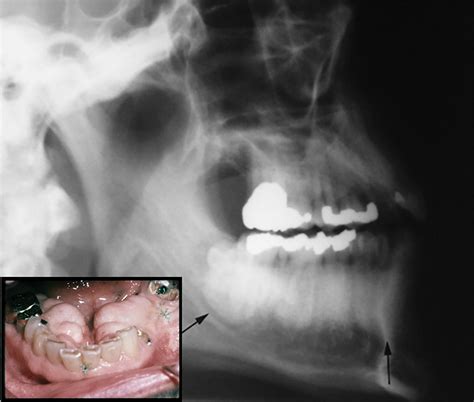

• Torus Palatinus: These occur on the roof of the mouth (hard palate), usually in the center. They can range from flat and wide to lobulated and prominent.

• Torus Mandibularis: These appear on the lingual (tongue-side) aspect of the lower jaw, usually above the mylohyoid line. These are often bilateral, meaning they appear on both the left and right sides of the lower jaw.